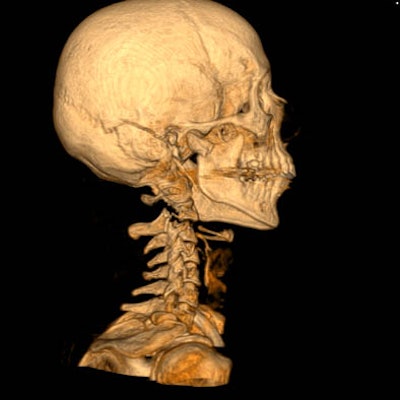

| A traffic accident victim suffered from multiple fractures and died from a broken neck vertebra (below). Images courtesy of Dr. Anders Persson and Patric Ljung. |